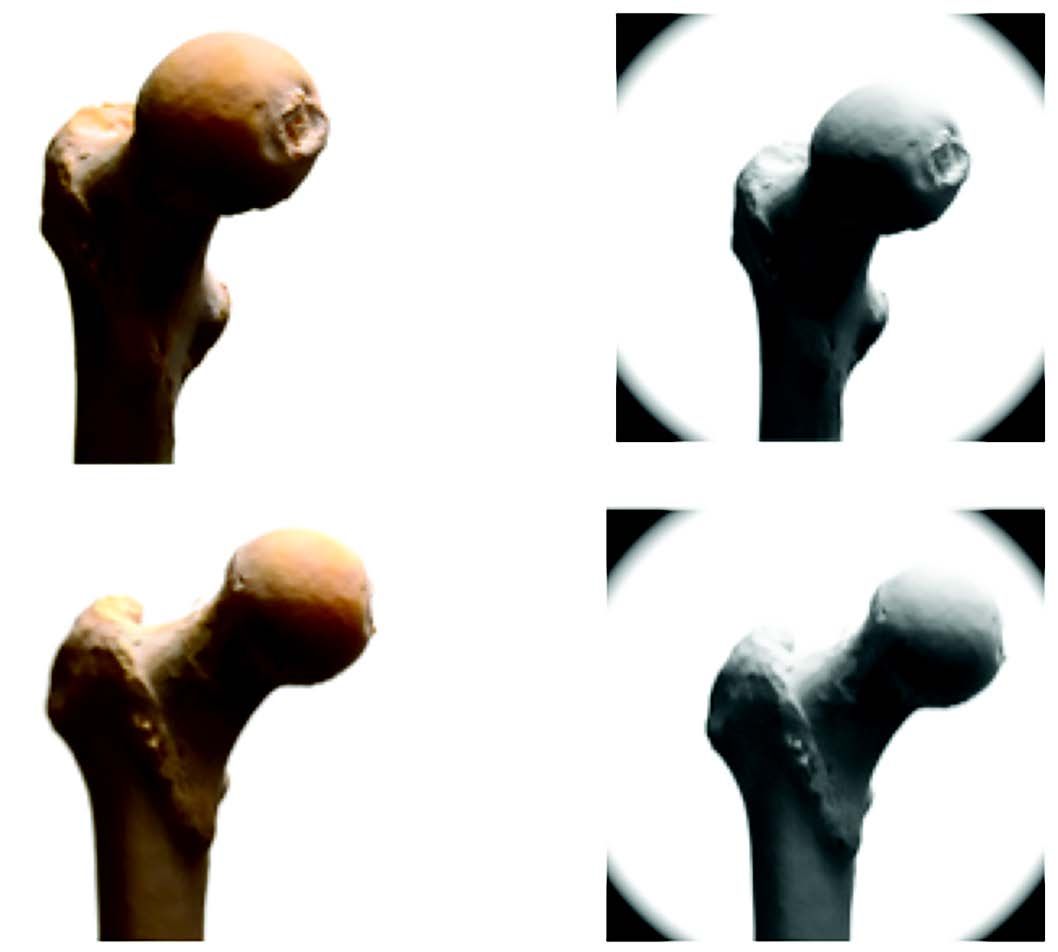

The CT-scan regularly shows that a hip which seems to be a short neck coxa valga is in fact a long neck coxa vara (Fig. 9 a and b).

CT-based preoperative planning was used for 392 records out of 472 arthroplasties performed from 2008 to 2014. Standard x-ray is still used for elderly patients and for second side surgery. The software makes it possible to use several types of implants, including a 129° self-locking straight stem. I now always use this stem when I can, the 129° angle corresponding to the mean value of a CT database (Fig. 1).